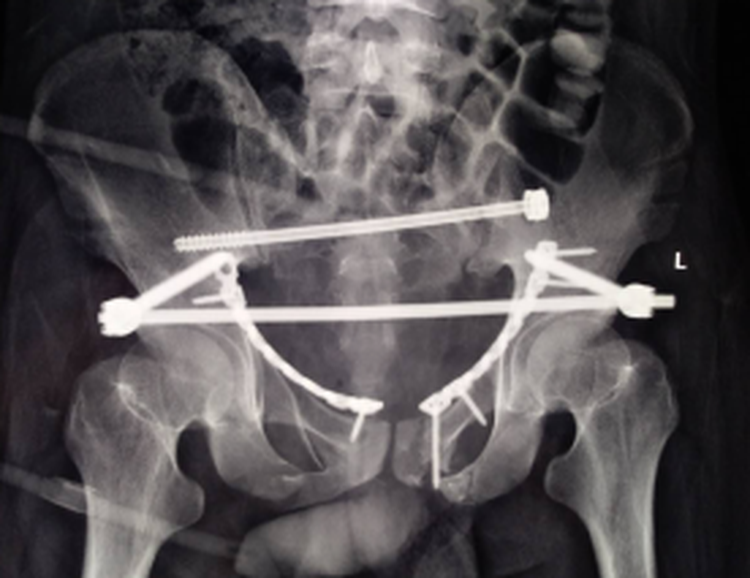

近日,我院骨创伤二科张鹏主任团队在北京301医院创伤骨科陈华教授的指导下,圆满完成了两例复杂骨盆骨折,两例手术都非常成功,术后病人恢复正常。

以往骨盆手术,传统手术方法需切开多个大型切口,肌肉组织剥离广泛、出血多,应用骨盆骨折闭合复位微创技术后,只是几个小切口,出血量减少至50ml以内,且基本不造成肌肉软组织损伤,手术时间缩短,使患者不必再忍受传统手术大切口的痛苦,而且能够确保骨折部位的精准复位和牢固固定。术后两名患者病情日渐好转。

张鹏主任表示,骨盆骨折微创治疗是目前骨盆骨折的最佳治疗法,为患者的生命安全和功能康复提供了保障,提升了我院创伤骨科的综合治疗水平。